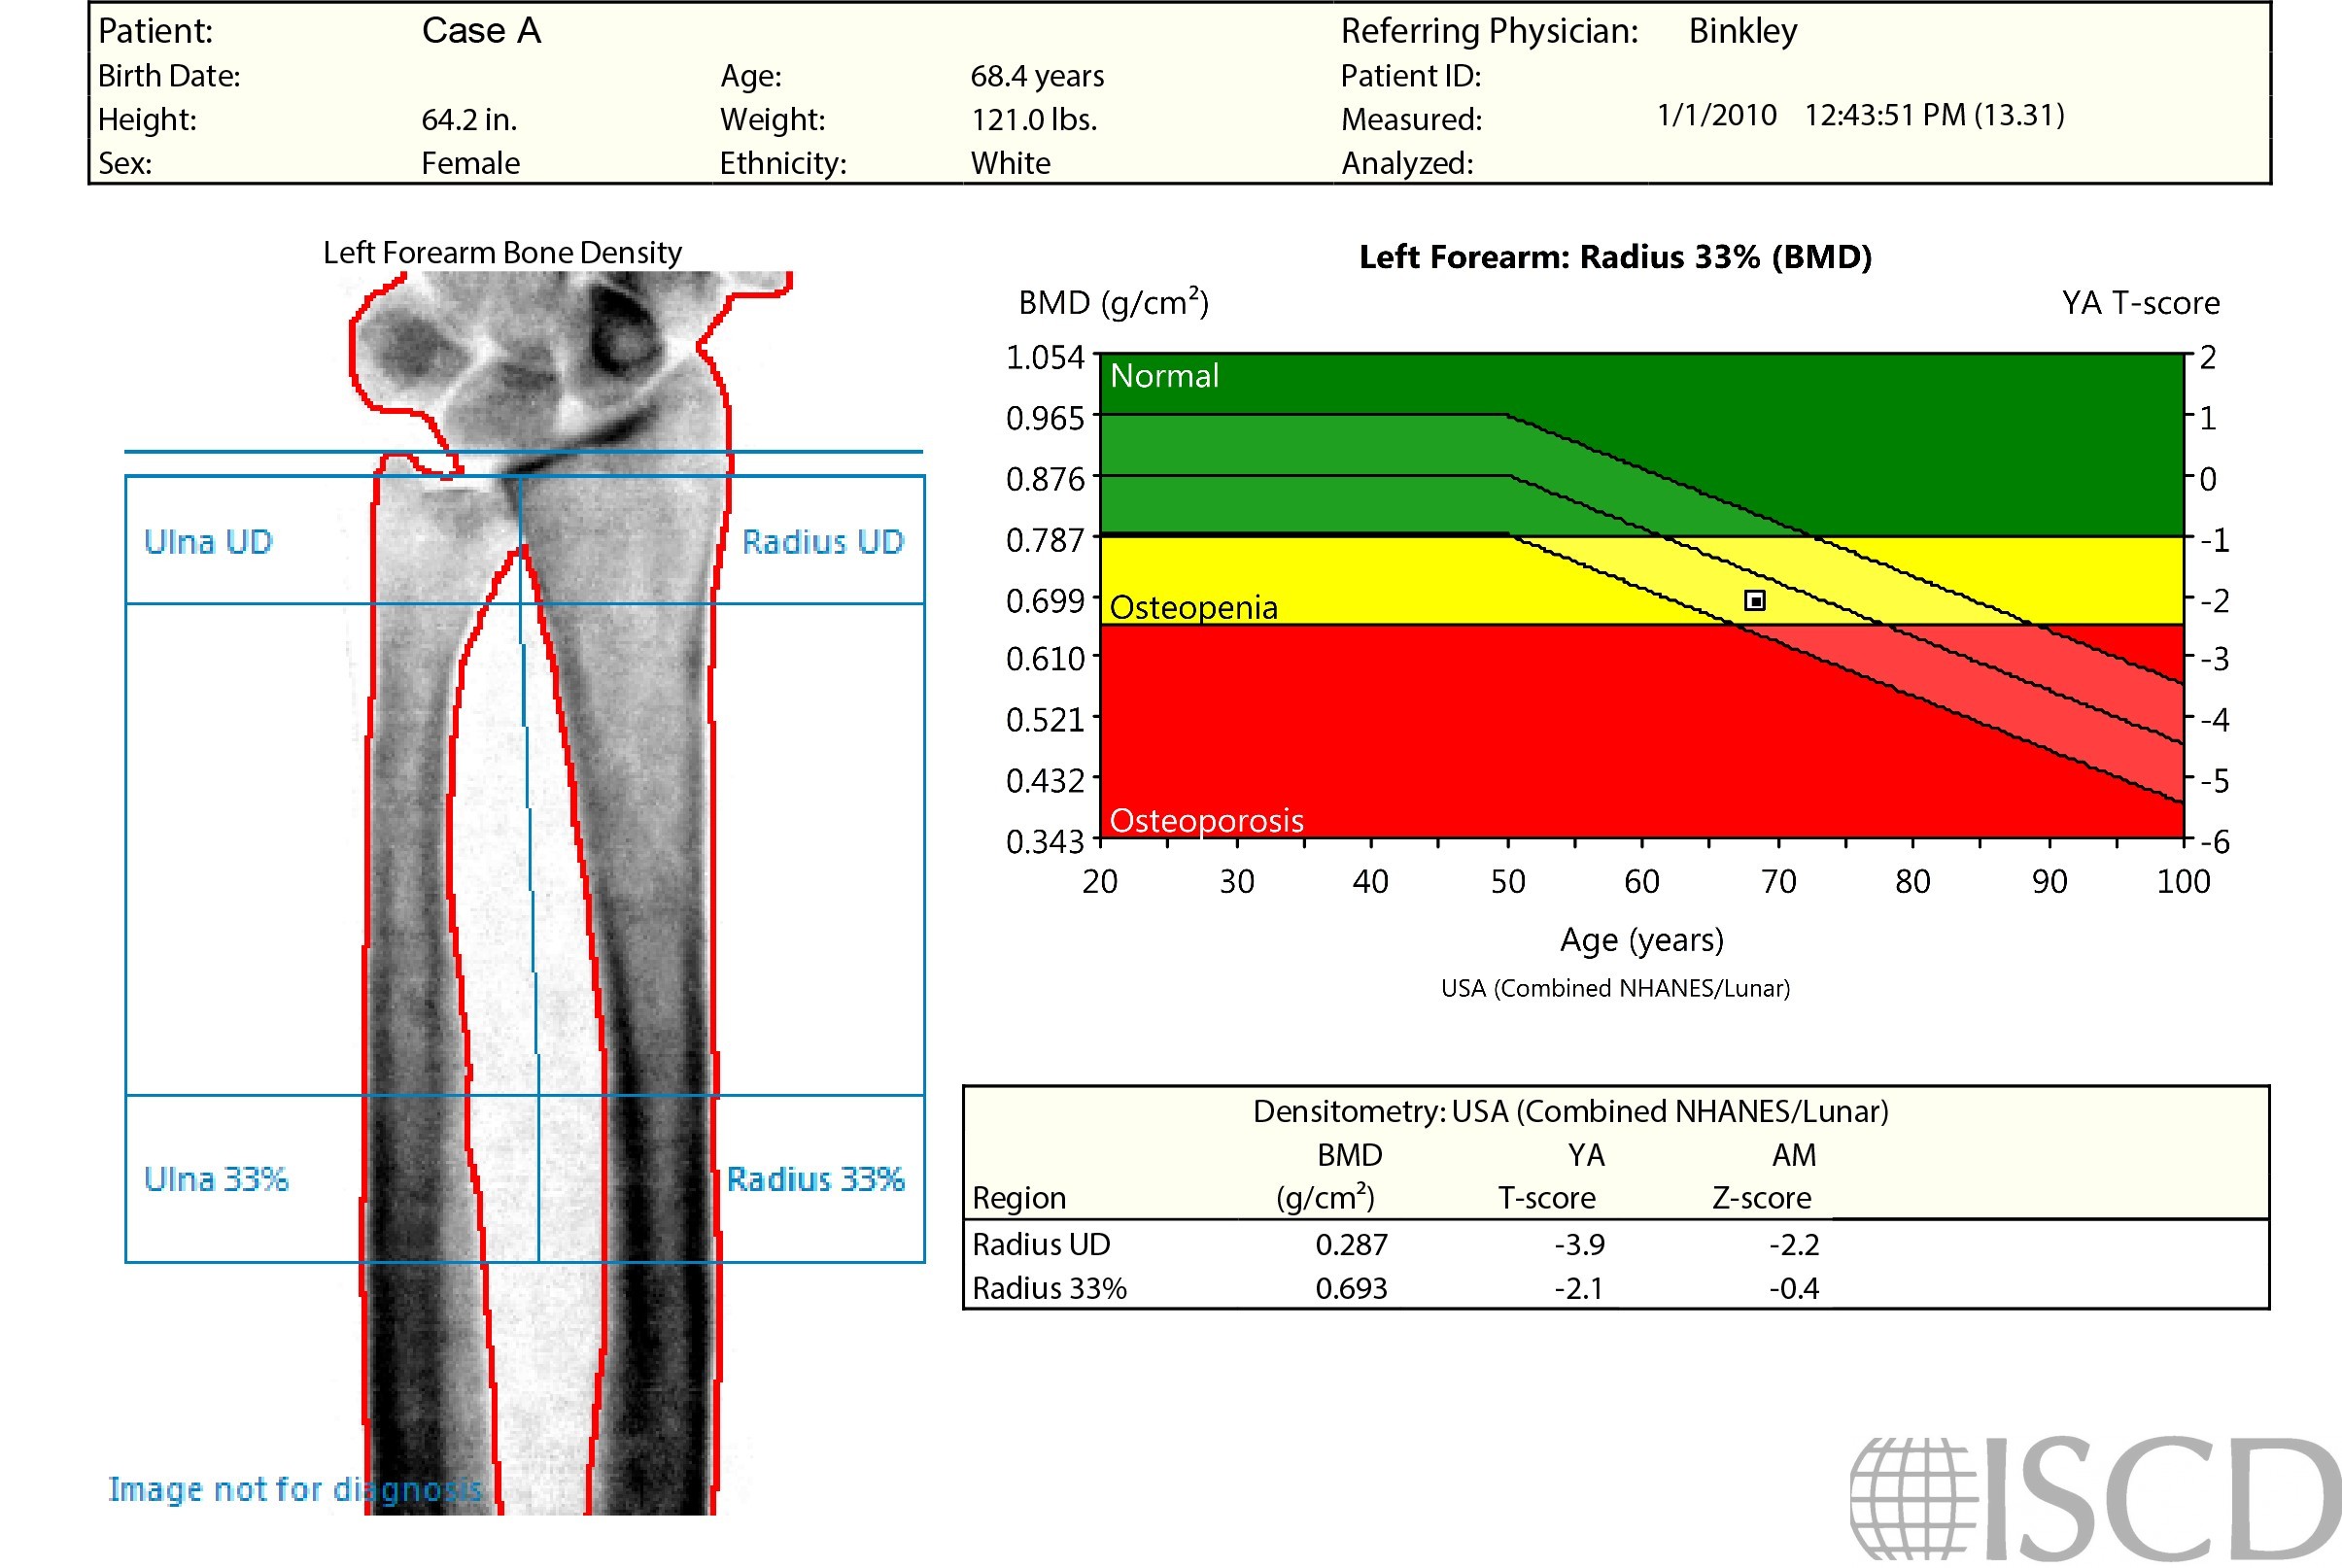

This is a set of precision scans acquired on the same day. On the top, BMD = 0.790 g/sq cm and T = -1.0 in the Radius 33%. On the bottom, BMD = 0.693 g/sq cm, T = -2.1 in the Radius 33%. The images appear to be well acquired. Observe the white oval in the upper left corner of the image on the left. This is air from the slot in the forearm positioner.

The point typing image indicates that the identification of bone is identical between both scans. Tissue point-typing demonstrates the problem, not only the patient’s arm, but the board are being measured as the soft tissue baseline. These different measurements in the respective BMD calculations result in the BMD difference observed from the reports.

Given the difference in densities between the positioner slot and the positioner, the software identified just the slot as air on the left. The scan on the right had consistent density outside the arm, consequently, that entire region was classified as air. This slot artifact only occurs when the slot covers the entire width of the first swipes at the very beginning or end. The recommendation is to always check the point-typing of forearm scans.

On a GE Healthcare scanner, the inclusion of positioner slots (where Velcro can be attached to the positioner) at the distal edges of the scan field can lead to soft tissue identification inaccuracies and incorrect 1/3 radius bone density measurements. It is recommended that technologists avoid slot inclusion in forearm scans, and point-typing should be evaluated as a part of routine analysis.